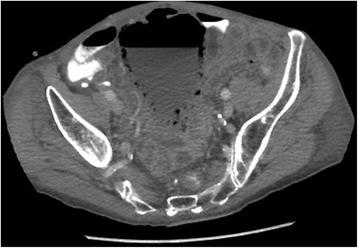

Emphysematous cystitis is a very rare complicated urinary tract infection characterized by air in the bladder wall.

We report two clinical cases of emphysematous cystitis of an 83-year-old Caucasian woman with diabetes mellitus and a 78-year-old Caucasian man with no past medical history. They presented with severe confusion and abdominal distension. Emphysematous cystitis was diagnosed in time with a thorough physical examination, urine analysis and computed tomography. The patients were successfully treated with antibiotic therapy and bladder drainage.